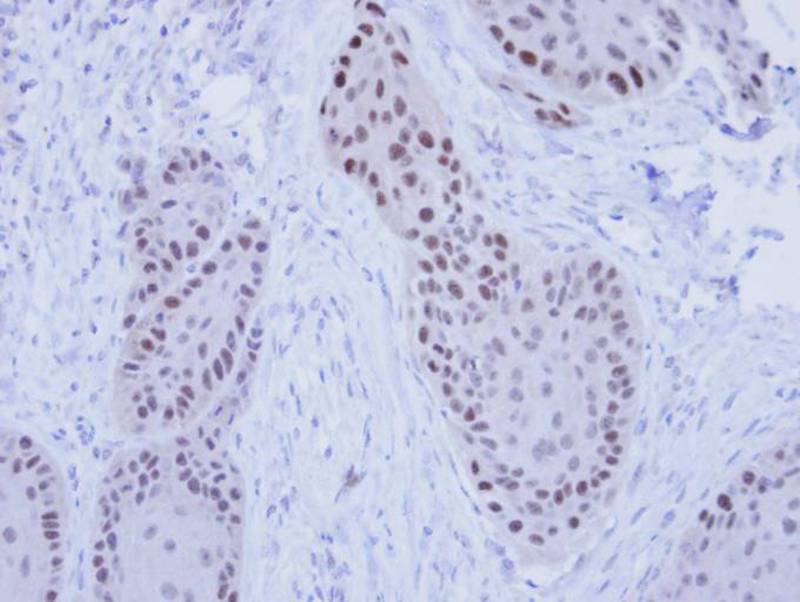

Immunohistochemical analysis of paraffin-embedded MDAMB-468 Xenograft, using RFC4 antibody at 1: 100 dilution.